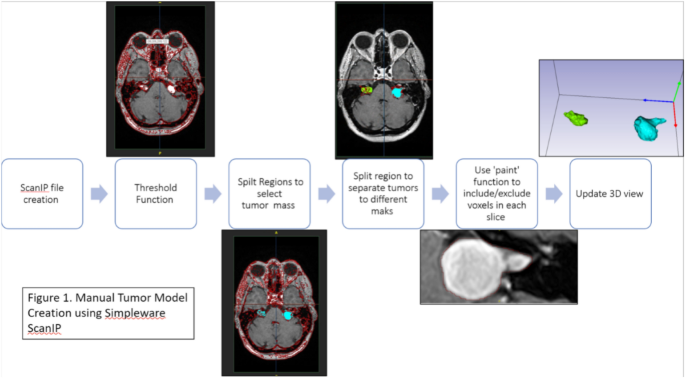

3D tumor masks were created for vestibular schwannomas (unilateral or bilateral) as follows (Fig. 2):

To highlight the vestibular schwannomas, a thresholding algorithm was used on selected slices containing the tumor mass. A ‘split regions’ algorithm was used to isolate the tumors and remove the non-tumorous voxels. Consideration was taken with voxels lining the border of the mask. Missing and surplus voxels were adjusted to include or exclude as necessary using the paint function. After the initial mask creation, the tumors were re-examined in all three planes (coronal, axial, sagittal views) to correct for any missing or extra voxels. All the models were reviewed by a neuroradiologist, who made necessary adjustments.

The ‘volume’ measurement tool was used to calculate the 3D volume (in mm3) of each tumor mask. To visualize the shape, size, and pattern of growth of the masked tumors, a mask was created of the pons at the levels of the tumors.